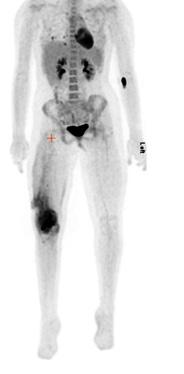

Sarcome d’Ewing

Le sarcome d’Ewing a été décrit la première fois en 1921 par James Ewing, cancérologue américain. C’est une tumeur osseuse à cellules rondes indifférenciées, plus précisément une tumeur neurœctodermique primitive. Il s’agit d’une tumeur extrêmement agressive, mais qui est très sensible à la radiothérapie. Il y aurait une translocation, c’est-à-dire une cassure ou une mutation dans les chromosomes 11 et 22. La maladie se localise principalement à la diaphyse de l’os long et parfois dans les vertèbres. La prédisposition serait 10 fois plus élevée chez les individus de race blanche plutôt que dans la population afro-américaine. Les données démographiques démontrent que ce sont les enfants qui sont les plus touchés ou les jeunes adolescents/adultes entre 5 et 20 ans, et il est extrêmement rare que ce cancer touche les gens au-delà de 20 ans. La prévalence est plus forte chez les garçons que chez les filles, et celles-ci ont de meilleurs taux de survie. Sur le plan radiographique, on décrit l’image du sarcome d’Ewing comme un « bulbe d’oignon », et la diaphyse est plutôt boursoufflée. Sur la scintigraphie osseuse (figure 1 ), la lésion apparaîtra plus